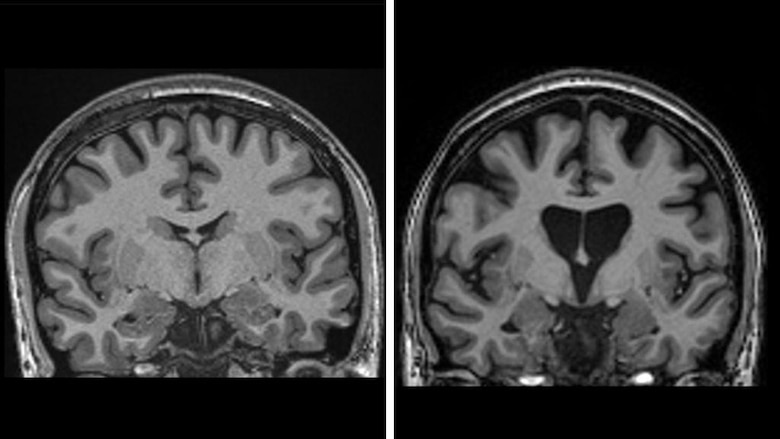

Los datos mostraron que, tres años después de la cirugía, se produjo una ralentización media del 75% de la enfermedad, según una medida que combina la cognición, la función motora y la capacidad para desenvolverse en la vida diaria.

También muestran que el tratamiento está salvando células cerebrales.

Los niveles de neurofilamentos en el líquido cefalorraquídeo, un claro indicio de la muerte de las células cerebrales, deberían haber aumentado en un tercio si la enfermedad hubiera seguido progresando, pero en realidad eran más bajos que al inicio del ensayo.